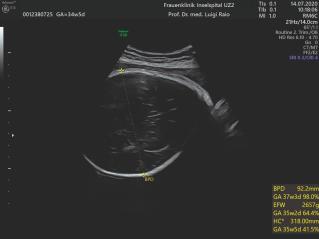

Sonoquiz - Was ist das?

Unauffälliger Verlauf der Schwangerschaft bei 42-jähriger Para 2, Gravida 4. Messung des BIP in der 37. Woche. Was fällt hier auf?